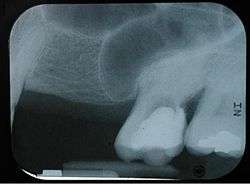

Maxillary sinusitis

Maxillary sinusitis is inflammation of the maxillary sinuses. The symptoms of sinusitis are headache, usually near the involved sinus, and foul-smelling nasal or pharyngeal discharge, possibly with some systemic signs of infection such as fever and weakness. The skin over the involved sinus can be tender, hot, and even reddened due to the inflammatory process in the area. On radiographs, there is opacification (or cloudiness) of the usually translucent sinus due to retained mucus.[3]

Maxillary sinusitis is common due to the close anatomic relation of the frontal sinus, anterior ethmoidal sinus and the maxillary teeth, allowing for easy spread of infection. Differential diagnosis of dental problems needs to be done due to the close proximity to the teeth since the pain from sinusitis can seem to be dentally related.[1] Furthermore, the drainage orifice lies near the roof of the sinus, and so the maxillary sinus does not drain well, and infection develops more easily. The maxillary sinus may drain into the mouth via an abnormal opening, an oroantral fistula, a particular risk after tooth extraction.